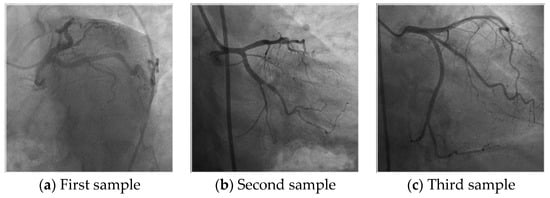

- Hidden biometrics is one of the popular research issues. This work contributes to the hidden biometrics research area and we investigated new biometric features in this work. To validate the human identification feature of the coronary artery images, a novel coronary angiography image database was collected and published publicly (see Section 2).

- To validate the results of the proposed coronary angiography images based on biometric identification, a new large database was collected and it is published publicly.